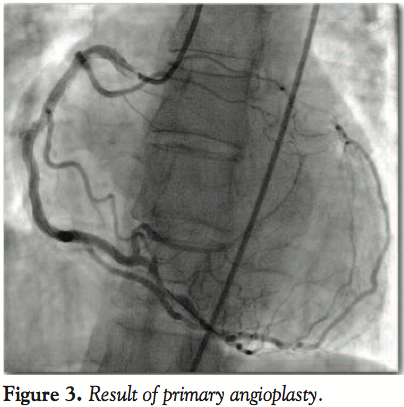

The ostium of the left main (LM) was absent on both attempted selective left coronary artery (LCA) angiograms and following aortography. RCA recanalization was performed using a JR 3.5 6 Fr guiding catheter. A Runthrough Hypercoat guidewire (Terumo) was passed through the occlusion up to the distal part of the RCA without difficulty. Successful thrombectomy (Figure 2) was performed with an Eliminate aspiration catheter (Terumo). A significant lesion in the proximal segment of the RCA was stented with a 4.0 x 28 mm Promus Element drug-eluting stent at 10 atm. Stenting effect was optimized with a 4.5 x 12 mm Quantum Maverick (Boston Scientific) at 12 atm achieved very good angiographic result (Figure 3). Low-pressure stent implantation followed by high-pressure NC balloon postdilatation is our policy to avoid edge dissection.